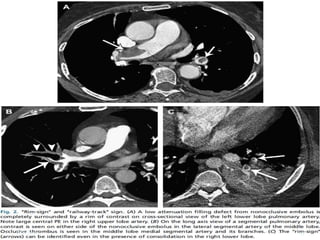

CT Angiogram

 Benefits                  Limitations

 Available             IV contrast

 Direct image          Expensive

 Alternative Dx        Patient

 Pelvic/leg veins       cooperation

 Uncertain

sens/spec

 “CT should not be used alone for

suspected PE, but combining tests

improves accuracy and reduces need for

angiography”